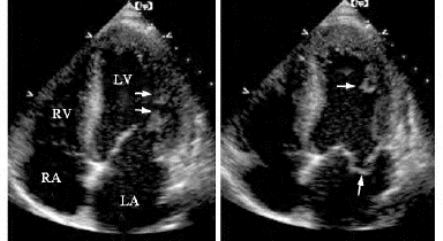

(1)室间隔肌部回声失落,连续中断,边缘不甚整齐(图19-14)。

2.彩色多普勒 收缩期五彩镶嵌血流信号由左室经穿孔处射入右室(图19-14)。

图19-14 室间隔穿孔的二维超声和彩色多普勒图像

左图显示室间隔中部连续中断;右图显示经左室穿孔处向右室喷射的五彩镶嵌分流束(见彩图28)